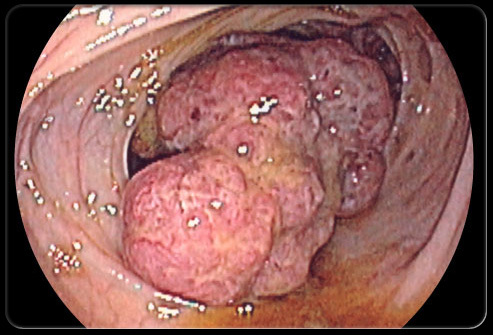

Q

Coloscopie pour bilan d’anémie ferriprive. qu’est ce que c’est?

A

tumeur colique